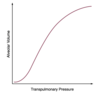

Click on the region of the alveolar compliance curve where ventilation is the greatest.

Alveolar ventilation is a function of alveolar size and its position on its compliance curve (Alveolar compliance = Alveolar volume / Alveolar Pressure).

The best ventilated alveoli are the most compliant.

They exchange more gas, because their volumes change more throughout the respiratory cycle.

These alveoli reside at the steep slope of the curve.

The least ventilated alveoli are the least compliant.

They exchange less gas, because their volumes change very little throughout the respiratory cycle.

These alveoli reside near the top of the curve.

A patient is scheduled for a VATS with lung resection. Click on the alveolar compliance curve that BEST illustrates what happens after he is anesthetized and placed in the lateral decubitus position.

When the anesthetized patient is placed in the lateral decubitus position:

The nondependent lung moves from the flat (noncompliant) region of the curve to an area of better compliance. Ventilation is best here, because the lung is on a favorable position of the curve.

The dependent lung moves from the slope (highly compliant) to the lower, flatter area of the curve. In this region, the reduction of alveolar volume contributes to atelectasis. Perfusion is best here due to gravity.

The net effect is that ventilation is better in the nondependent lung and perfusion is better in the dependent lung. This creates V/Q mismatch.